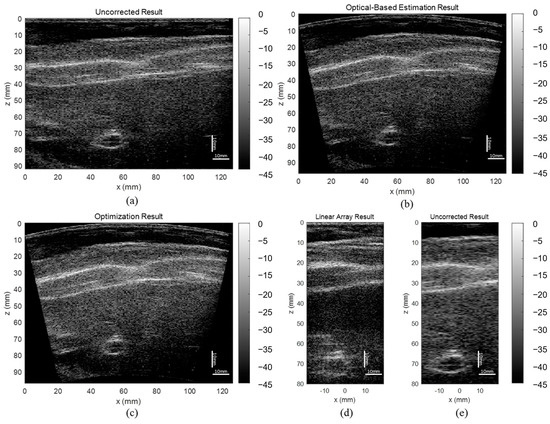

3.2. CIRS Phantom Results

The uncorrected, optical-based estimation, and optimization results of the CIRS phantom are shown in Figure 9. The results illustrate that without any correction on array shape, the reconstructed image will have strong defocusing and distortion, while both proposed algorithms can correct these effects. The lateral FWHM of the point scatters in different depths are plotted in Figure 9d. The averaged lateral FWHM of the uncorrected, estimation, and optimization results are 6.04 mm, 2.42 mm, and 2.75 mm, respectively. The aspect ratio, CNR, and GCNR of the center hyperechoic cyst and the second left anechoic cyst are listed in Table 4. Both corrected results have significantly lower distortion and higher contrast than the uncorrected result. Specifically, analyzing the cysts in the CIRS phantom, the optimization result has a more accurate shape, clearer boundary, and higher contrast compared with the optical-based estimation result. Therefore, it is believed that the shape optimization algorithm has the overall best performance on estimating the array shape.

Figure 9.

Reconstructed images of the CIRS phantom (a) without array shape correction, (b) with optical-based estimated shape, and (c) with optimized shape, and (d) line plot of lateral FWHM of the point scatters.